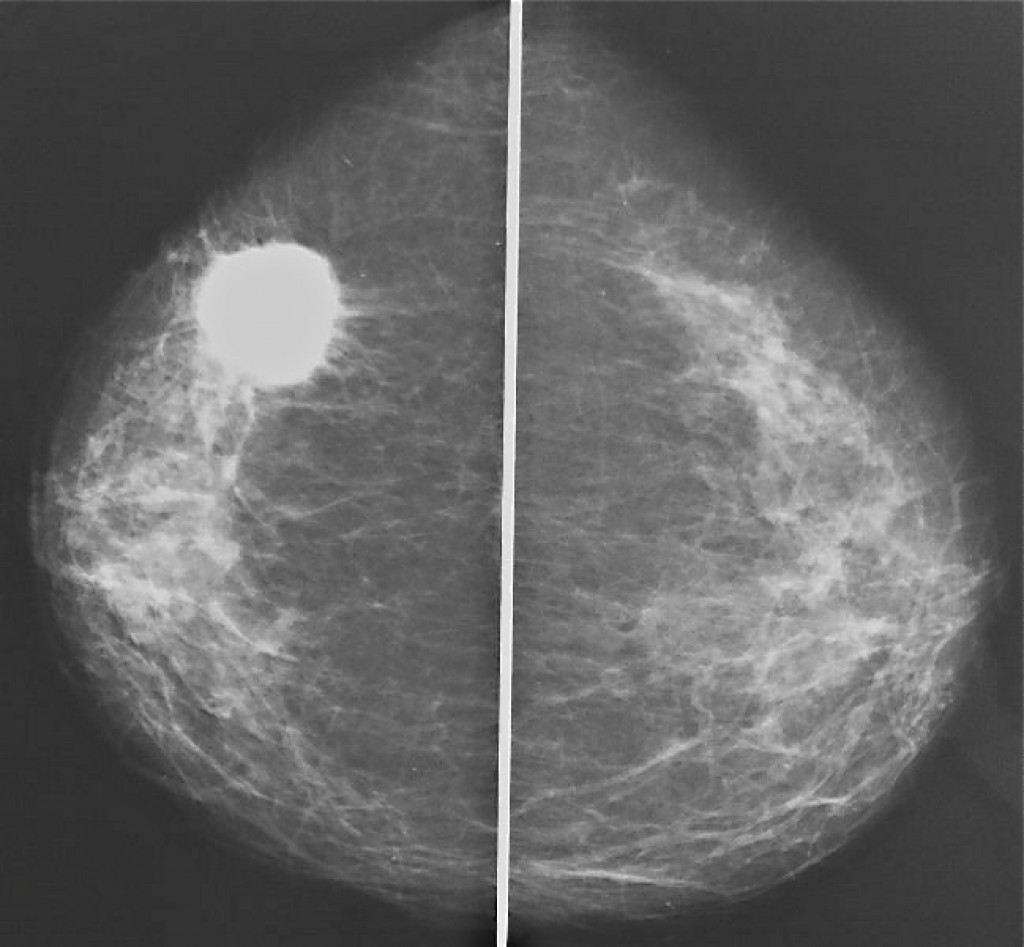

Феномен гипердиагностики в маммографии: примеры и иллюстрации

Раздел: Образы вокруг